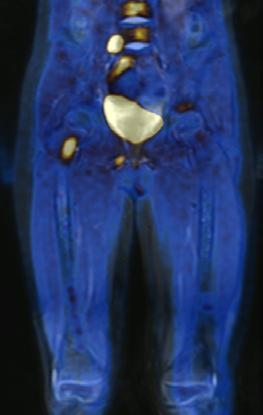

zo de [131I]mIBG en la evaluación del neuroblastoma mIBG-negativo o débilmente mIBG-positivo, y como modalidad complementaria cuando las imágenes radiológicas o los hallazgos clínicos sugieren una enfermedad más extensa que la revelada por las imágenes [131 I]mIBG. Con el desarrollo de otros blancos moleculares específicos para la detección de lesiones en neuroblastoma, entre ellos; [18F] Octreotide y 6[18F]F-DOPA (Figura 3) se puede obtener mayor especificidad y sensibilidad que la gammagrafía convencional con [ 131 I] mIBG, además de menor exposición a la radiación principalmente en glándula tiroides.

Estudio PET con 6-[18F]DOPA 3A) y [18F]OCTREOTIDE 3B) en cortes coronales de secuencias T2 de miembros pélvicos y con imágenes fusionadas, donde se identifica mayor sobreexpresión anormal de los receptores de somatostatina al compararlos con 6-[18F]DOPA, y que hace candidata a la paciente para PRRT.